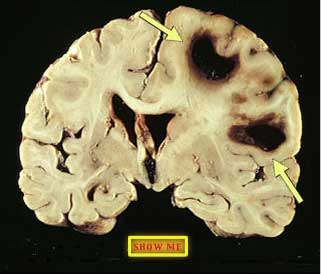

Locate the hemorrhages.

click to view answer